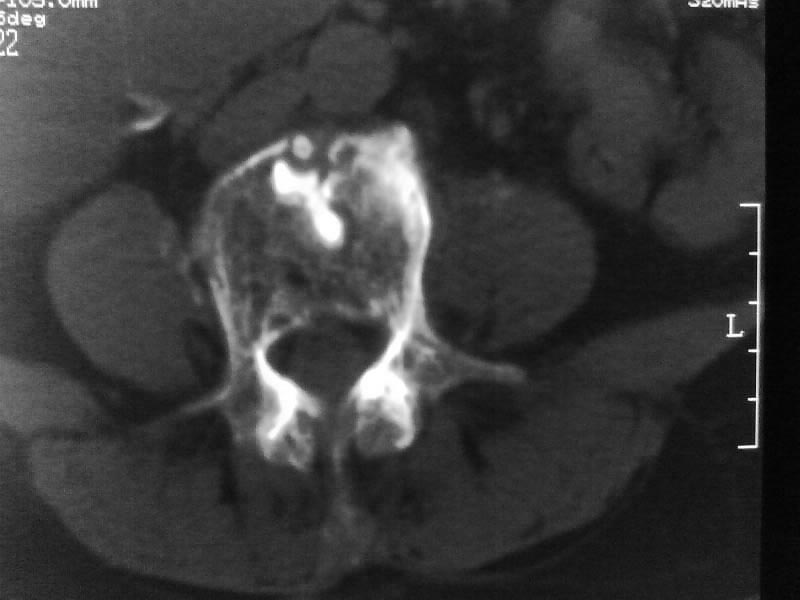

定位相示l2呈楔形改变(ct示陈旧性骨折改变,图像未传),l4.5椎体融合,以下是l4.5ct平扫.请各位看看,

考虑结核(有破坏、硬化及死骨)。

1、三四椎体结核,2、水平骶椎。

1、l1压缩性骨折(陈旧性)。

2、l3、4椎体结核。

就是腰1压缩性骨折,腰3\\4椎体结核(融合),水平骶椎.

支持 l1椎体陈旧性压缩性骨折;l3、4椎体结核(融合);水平骶椎。